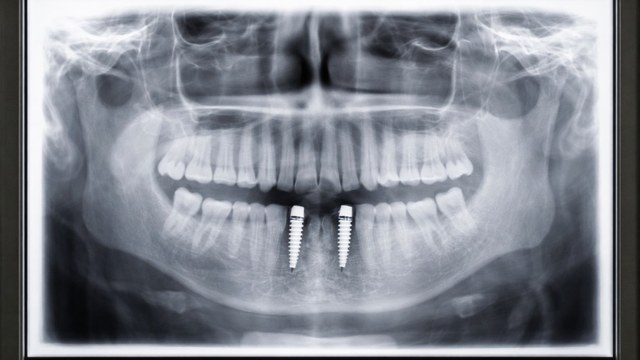

שתל דנטלי הינו תחליף מלאכותי לשורש שן המהווה בסיס לחיבור ועיגון אלמנט שיקומי כגון תותבת או כתר. שתלים דנטליים לרוב עשויים סגסוגת (תרכובת מתכות) טיטניום וצורתם דמויית בורג. מדובר בדרך הטובה ביותר הקיימת כיום להשלמה של שיניים שאבדו. השתל הבורגי מוחדר אל העצם האלואולרית Alveolar bone ע"י קידוח של חריר והברגתו של השתל פנימה כך שבסיום ההברגה השתל כולו מוקף ונמצא בעצם. החיבור של הטיטניום אל העצם יוצר קשר מבני ופונקציונלי בין העצם החיה לבין השתל. במקרים של חוסר עצם יתכן ונאלץ לבצע השתלת עצם BONE AUGMENTATION.